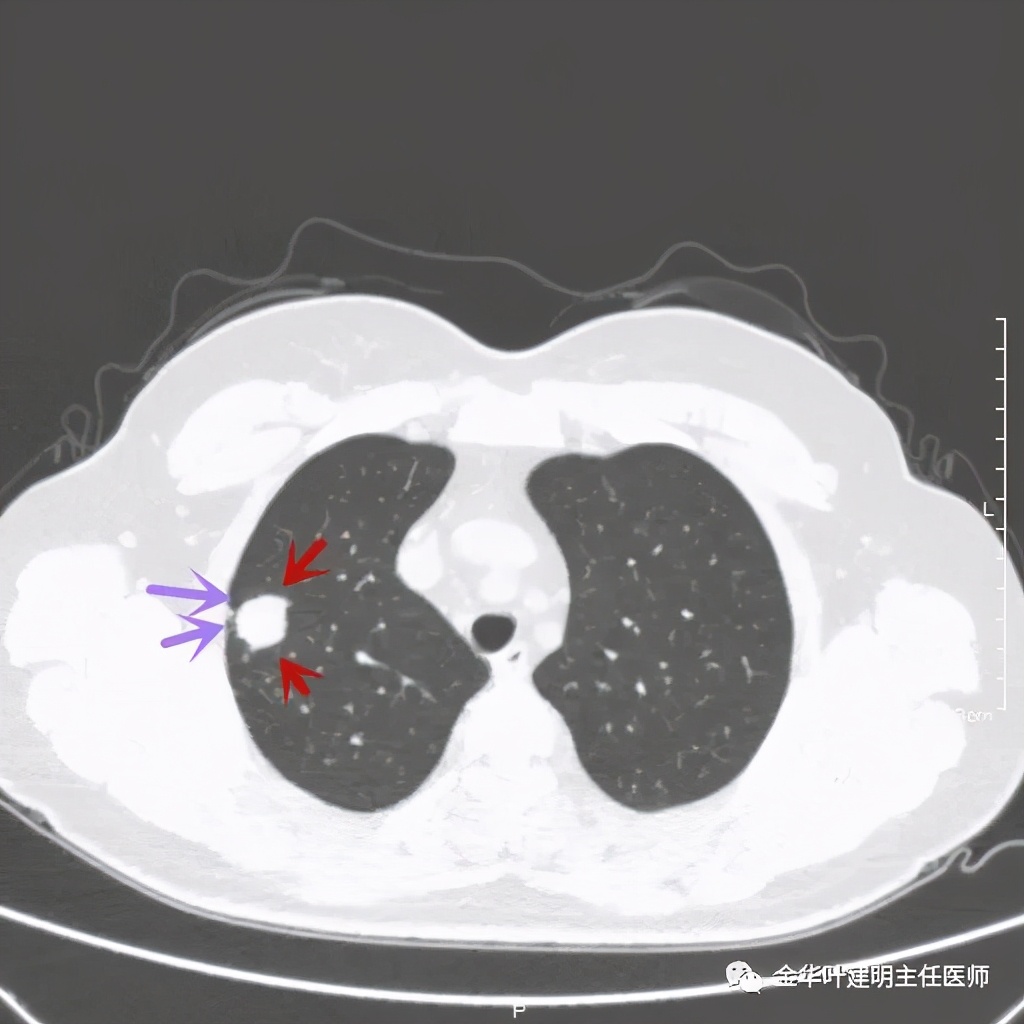

紫色箭头示病灶与胸膜很近,但无牵拉凹陷,绿色箭头示附近有微小其他病灶

绿色箭头示病粉旁边有卫星灶,而且密度都高,主病灶也是实性

病灶边散在多发微小实性与似磨玻璃的微小结节

病灶附近不清爽